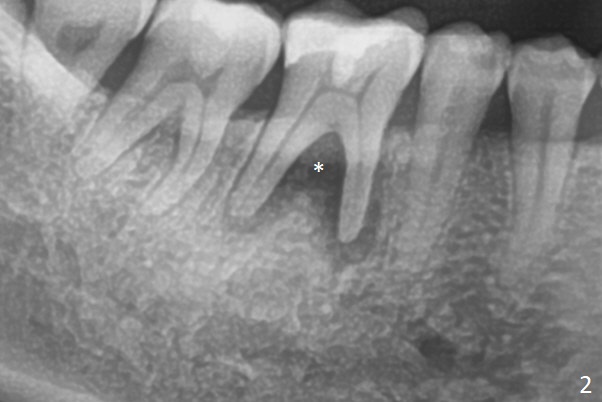

A 45-year-old man fractures the distolingual cusp of the tooth #30 subgingival (Fig.1). In fact RCT restores the septal bone, as compared to Fig.2. Initial depth at the septum is 13 mm (Fig.3).